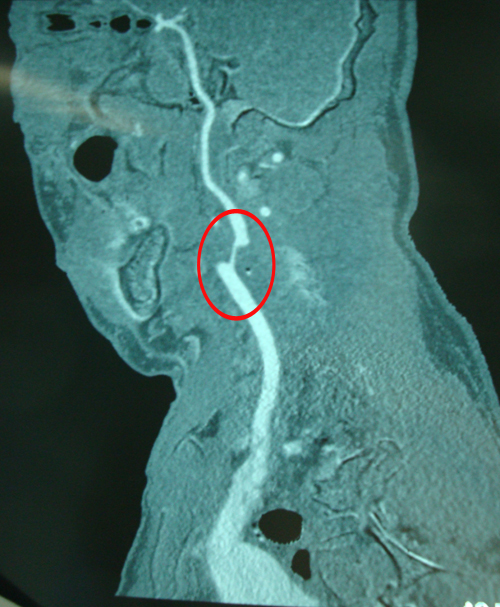

头部血管CT造影:右侧颈内动脉颅内段、右侧大脑中动脉水平段可见节段性狭窄(中度),右侧颞叶、顶叶灌注较对侧偏低。

颈动脉CTA:双侧锁骨下动脉,右侧颈内动脉开口,右侧椎动脉开口局限性狭窄,病原性质考虑动脉硬化性。

双侧颈动脉正位片

右侧ICA